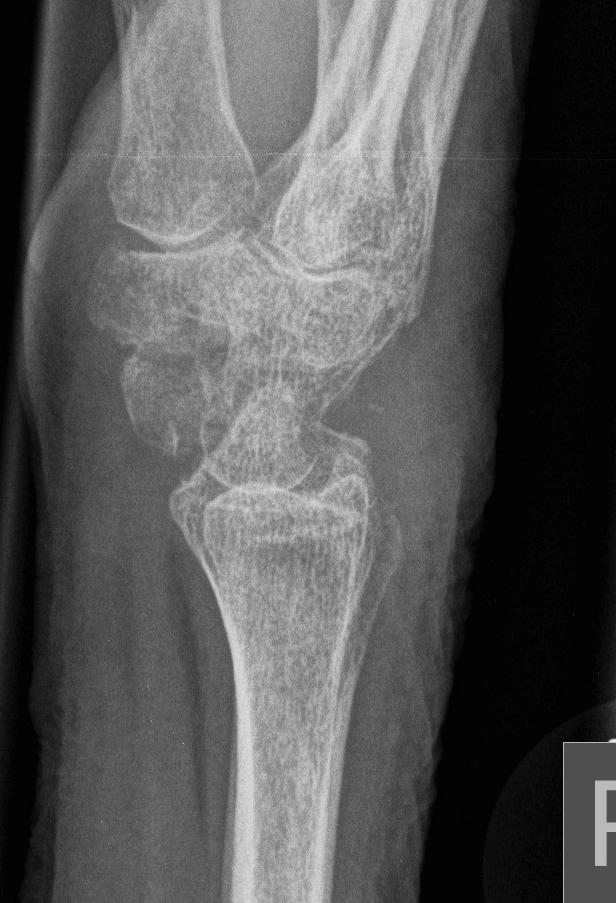

Definition

Scaphoid non union advanced collapse

Diagnosis

Xray / CT

- non union of scaphoid

- radio-scaphoid OA